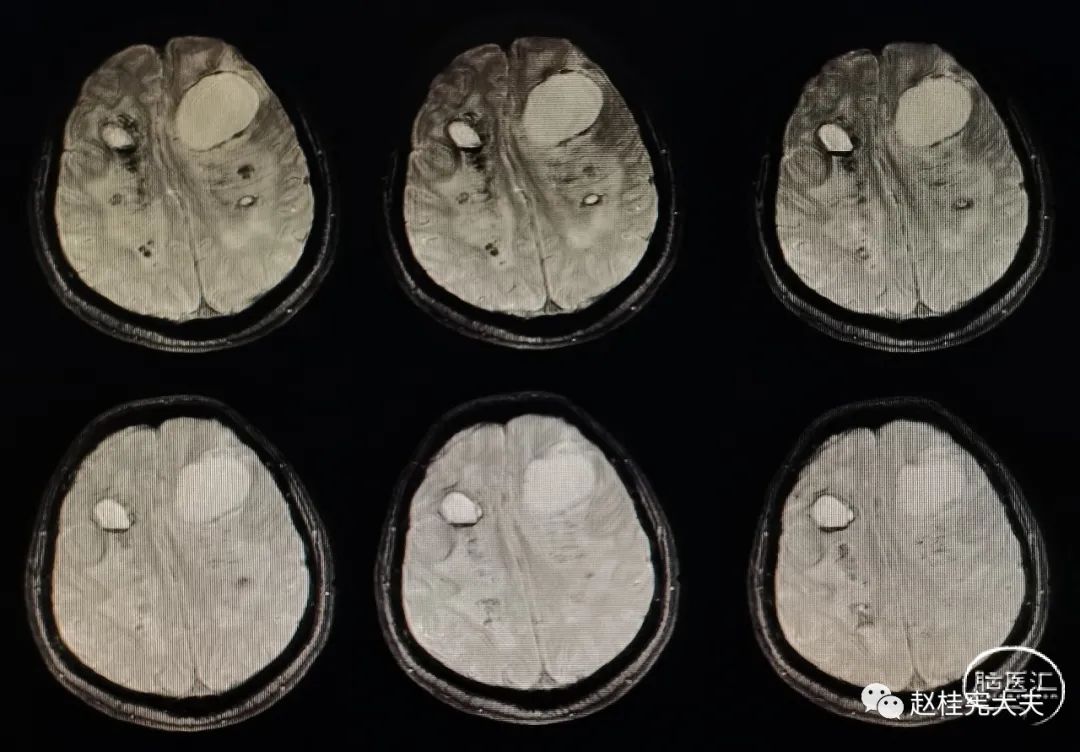

专病门诊时间,家属带患者来就诊。病史很简单,女性患者,56岁,以“反复头痛8年,加重2月”就诊。患者于8年前因头痛查颅脑CT提示颅内多发低密度影,行颅脑磁共振平扫+增强提示颅内多发病变,多个小囊,脑白质病变,病灶部分不规则强化,当地医院以寄生虫病服用打虫药3个疗程,症状同前,复查颅脑磁共振病灶未见明显变化。后未进一步诊治。2021年9月,因头痛加重,再次复查头颅磁共振平扫+增强提示颅内多发较大囊肿,弥漫性脑白质病变,再次查寄生虫抗体均阴性。目前诊断不明。